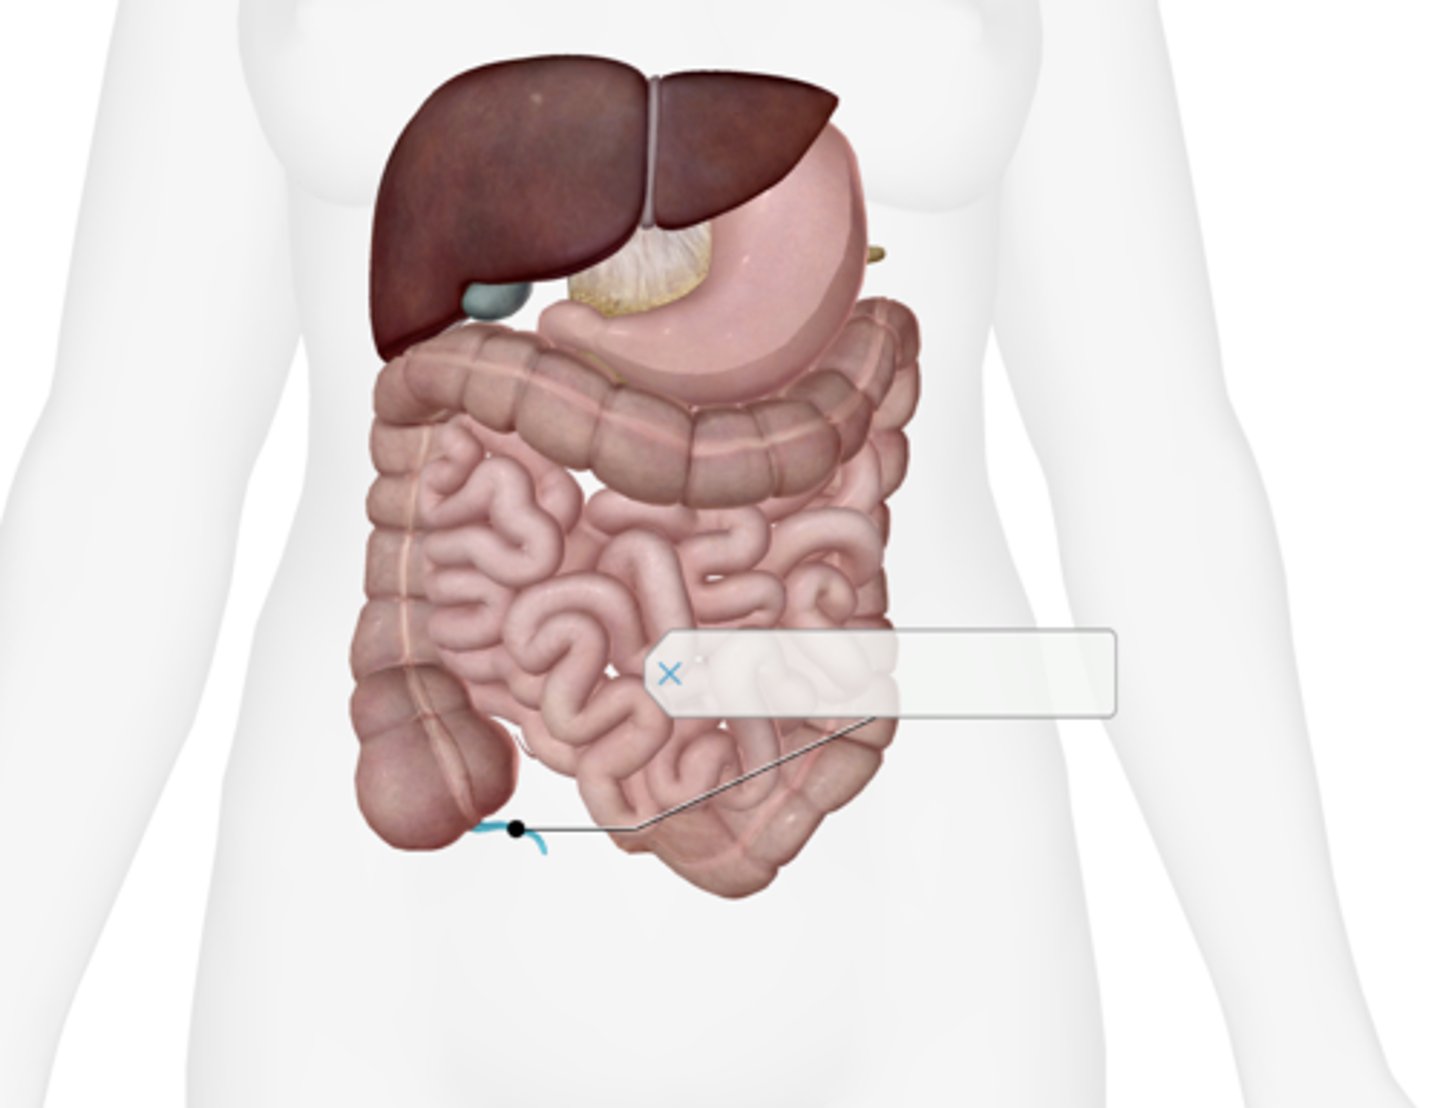

Appendix